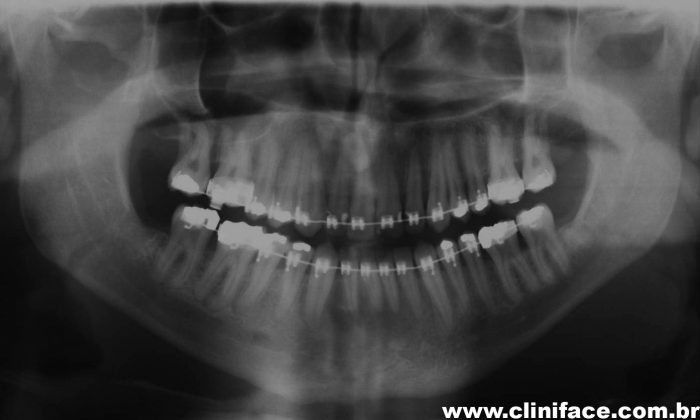

Raio X panorâmico inicial